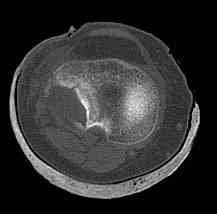

центральная импрессия, а при ипрессии с краевым переломом - после приподнимания импрессии опорная (Butress) пластина, как на снимке.